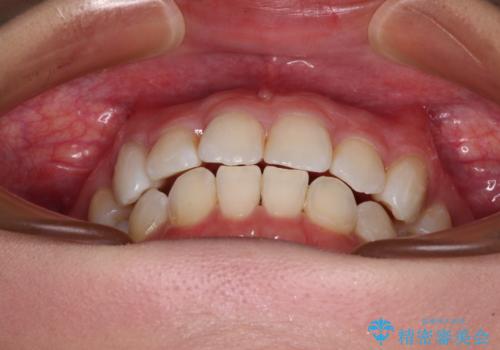

上顎の八重歯と下顎前歯の欠損 ワイヤー装置による抜歯矯正

下顎前歯と本来抜歯矯正で抜歯する歯とは大きさが異なるため、仕上がりの咬み合わせは理想的なものとはなりませんでしたが、気になっていた八重歯はきれいに改善することができました。